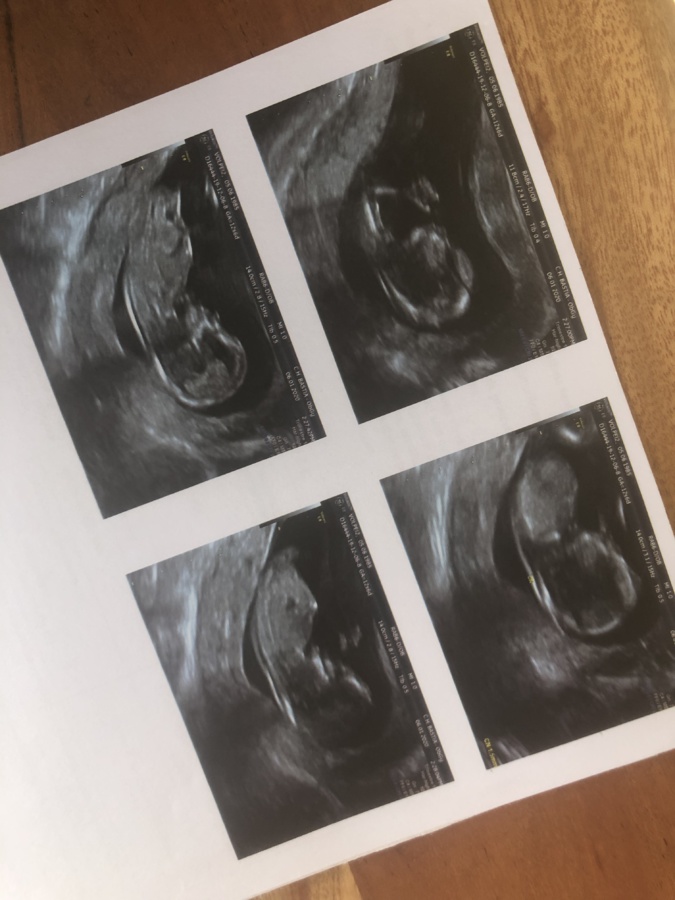

C'est notamment de devoir sortir de la maison pour faire des examens médicaux en lien avec la grossesse. Alors on fait attentions aux efforts quotidiens et on est, peut-être, plus qu'à l'accoutumé, attentive au moindre signe de notre corps. Le moindre tiraillement, la petite contraction de Braxton-Hicks met en alerte. Ce que je souhaite plus que tout c'est éviter le milieu médical et en réalité le monde en général. À dire vrai, j'évite même de faire les courses. C'est mon mari qui s'en charge. Oui, cela peu paraître légèrement agoraphobe ou hypocondriaque... Mais rendons nous a l'évidence, malgré les nombreux messages diffusés sur les risques encourus, de trop nombreuses personnes agissent de manière inconsciente voire même assassine. De ce fait, la plus grosse peur c'est tout simplement de contaminer mes enfants, le bébé à venir, être contaminée, hospitalisée, devoir les laisser ou que l'un d'entre eux soit hospitalisé, seul : c'est ça le pire !

Selon certaines études, le bébé ne peut être contaminé in utero, mais étant de 5 mois et demi, en cas d'insuffisance respiratoire on ne sait pas ce qui peut arriver...

D'un autre côté, ne pas pouvoir faire des examens aussi facilement qu'en temps normal peu également effrayer. Et oui, vive la contradiction intérieure !

Je suis stressée lors des déplacements gynécologiques obligatoires ou en cas d’urgence gynécologique. Bien que toutes les mesures d’hygiène sont prises par les professionnels de santé, on a toujours peur de contracter le virus. Le manque de recul effraye car bien que les études montrent que contracter le virus enceinte n’est pas nuisible pour le fœtus mais à cinq mois de grossesse on garde toujours en tête qu’une fièvre de plusieurs jours peut provoquer un accouchement prématuré et à ce stade le bébé ne survivrait pas. Sans Parler du fait que si on atteint le stade de viabilité et qu’on risque d’accoucher, vu qu’il n’y a pas de maternité de niveau 3 en Corse, on n’a aucune certitude dans le contexte actuel qu’on nous évacuerait pas sur Marseille ou Nice comme c’est le cas habituellement" ajoute Mattea Letulzeau, qui sera maman pour la première fois au mois d'août.